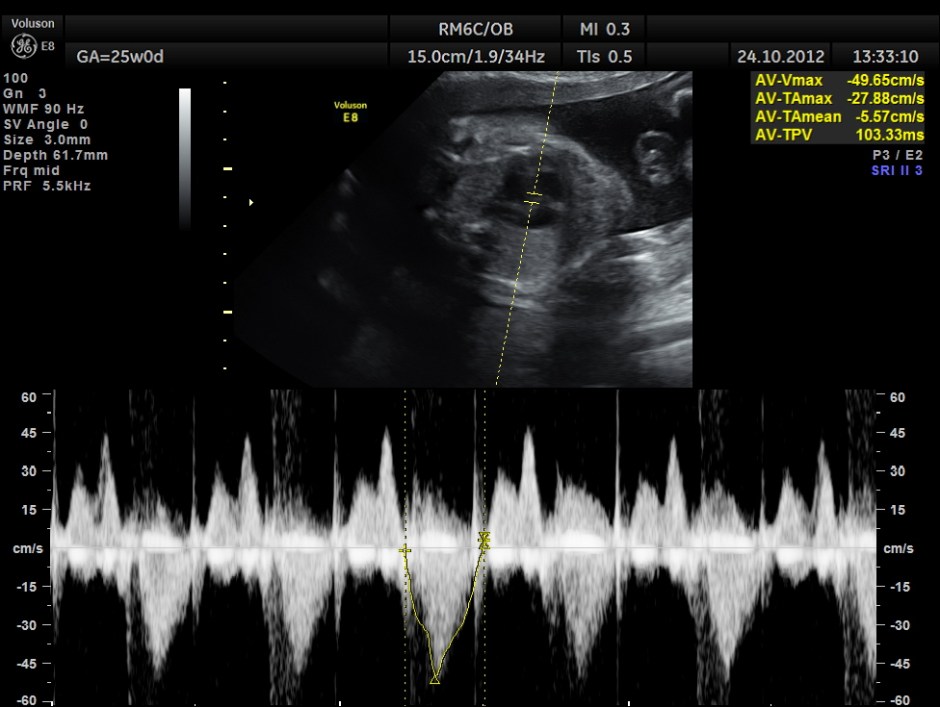

The scan was done around 25 weeks of gestation :

the following are spectral doppler flow across the 4 valves